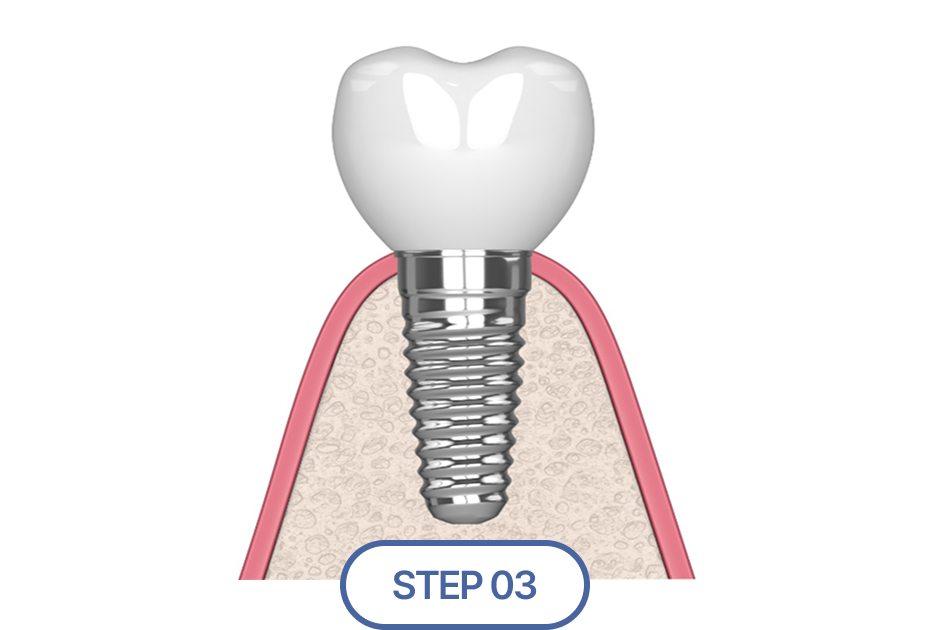

임플란트 식립 및 보철물 결합

식립이 정확하게 이루어졌다면,

그 위에 올라가는 보철물 또한 완벽해야 합니다.

저희는 획일화된 기성품 지대주 대신

환자 맞춤형 지대주(Custom Abutment)사용을 원칙으로 합니다.